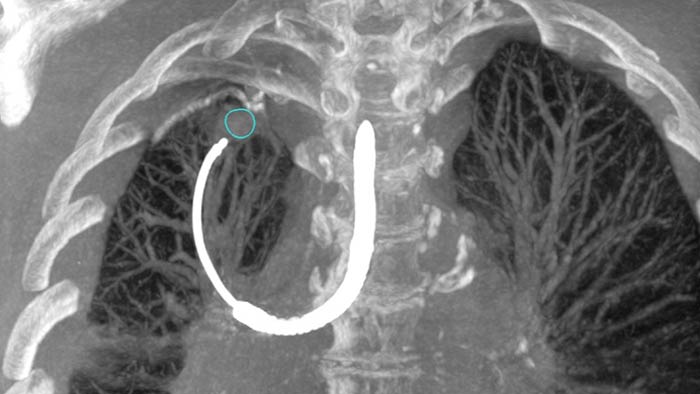

Los cirujanos e intervencionistas pueden obtener nuevos conocimientos para mejorar la atención al paciente con el apoyo de la guía de imágenes 2D y 3D líder en el mercado, el estricto control de infecciones y las medidas de gestión de dosis de rayos X. El sistema de terapia guiada por imágenes Philips Azurion es el corazón de su sistema de quirófano híbrido avanzado, lo que permite a los equipos clínicos aprovechar de forma fácil e intuitiva una gran cantidad de capacidades clínicas. Nuestras suites clínicas ofrecen una cartera flexible de tecnologías, dispositivos y servicios integrados para procedimientos cardíacos, vasculares, pulmonares, neurológicos y de columna vertebral como parte de su quirófano híbrido.

Soluciones para cirugía vascular con nuestros principales sistemas de imágenes, herramientas clínicas avanzadas y dispositivos vasculares. Todo ofrecido por la terapia guiada por imágenes de Philips.